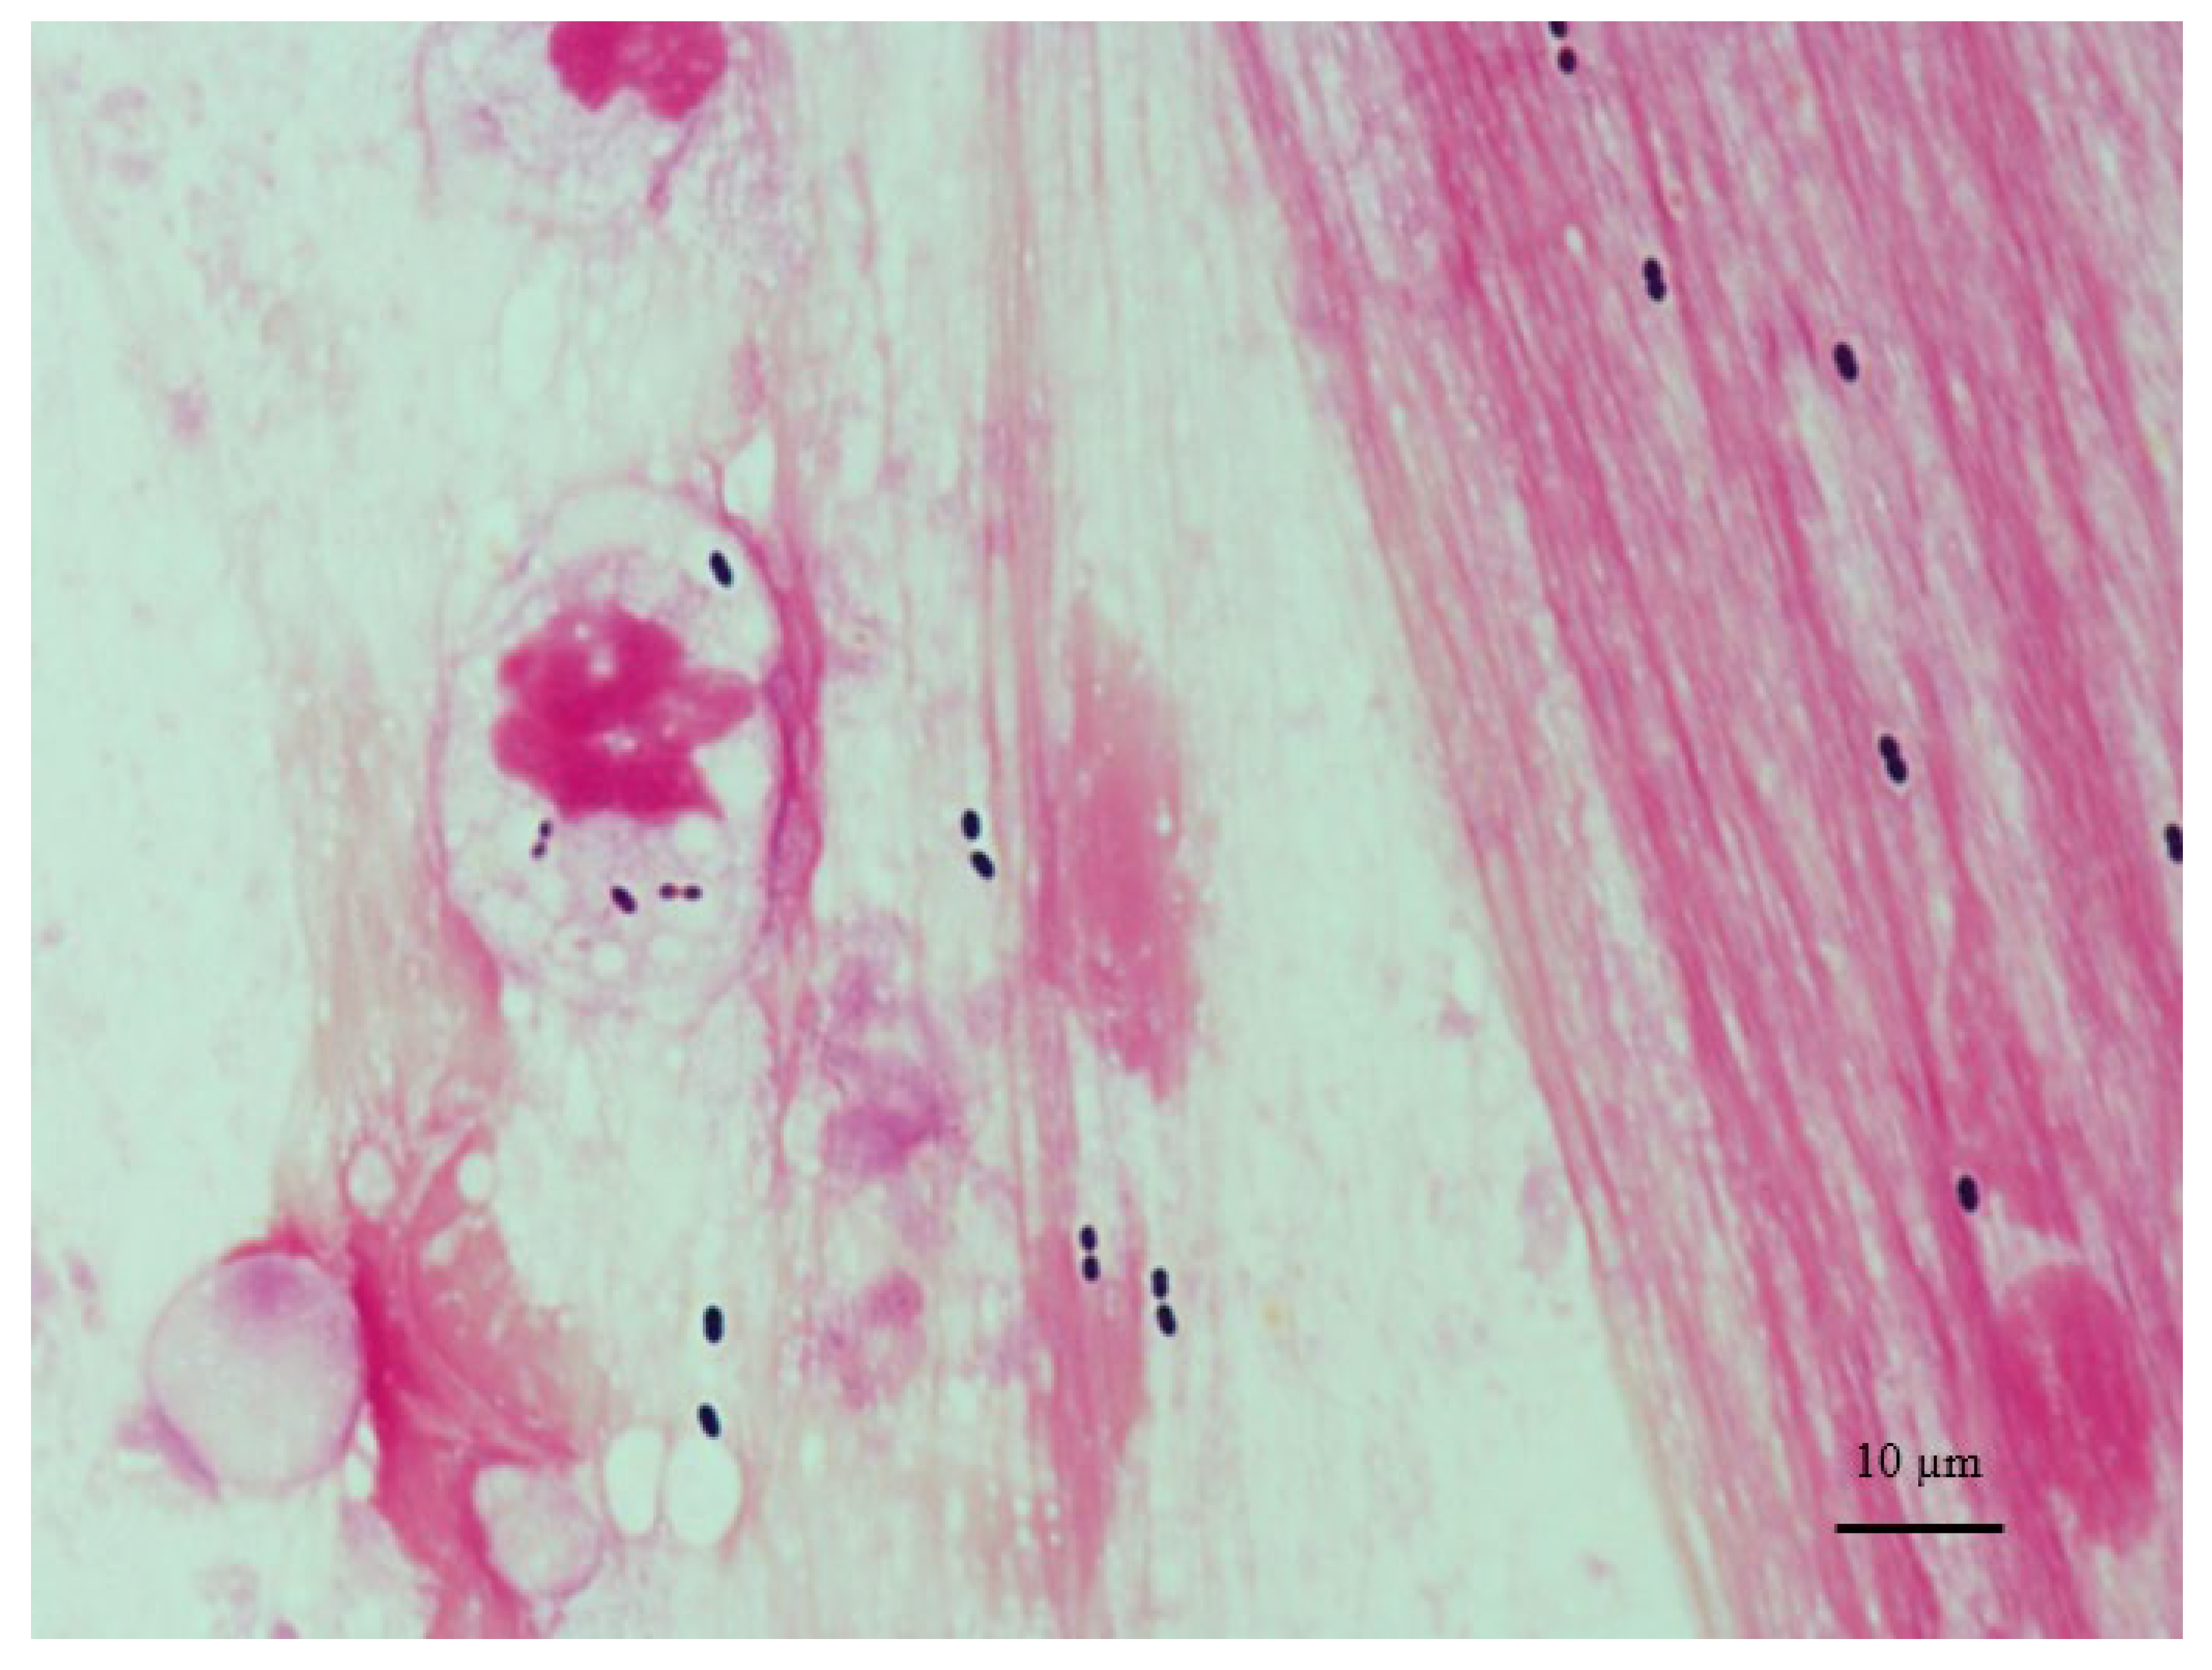

The bacterium, also called pneumococcus, was first isolated by pasteur in 1881 from the saliva of a patient with. Pneumococcaldisease and pneumococcal vaccines published date: Wc2645 live (ce for the live event expires october 21, 2019) wd2645 enduring (ce for the enduring event expires june 1, 2020) originally aired on september 18, 2019, 12 noon.